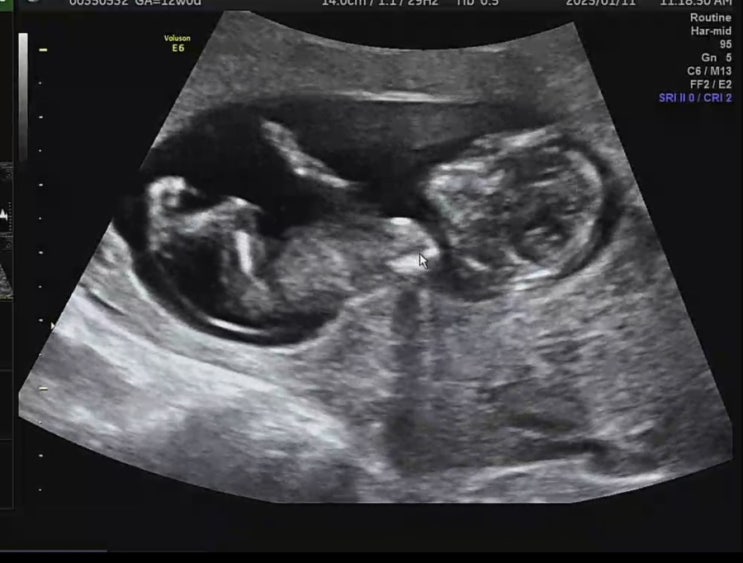

[12주]1차기형아검사/니프티검사/임산부 교통비 신청

#임신12주차 드디어 12주차가 왔다! 난임병원 졸업 후 동네병원으로 전원을 하고 진료를 보기위해 아침일찍...